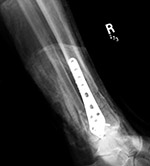

Dynamic compression plate and syndesmotic screw |

There is a six hole dynamic compression plate and a syndesmotic screw for an acute distal fibular fracture and syndesmotic injury. From Hunter, 1994 |